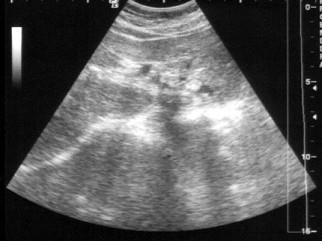

问题 患者女36岁,反复上腹部疼痛不适数10年,偶尔皮肤、巩膜黄染。B超检查如图所示,根据超声声像图,诊断为?(?)

选项 A.左肝内胆管癌 B.左肝内胆管蛔虫 C.左肝内胆管胆泥淤积 D.左肝内胆管结石 E.左肝钙化灶

答案 D